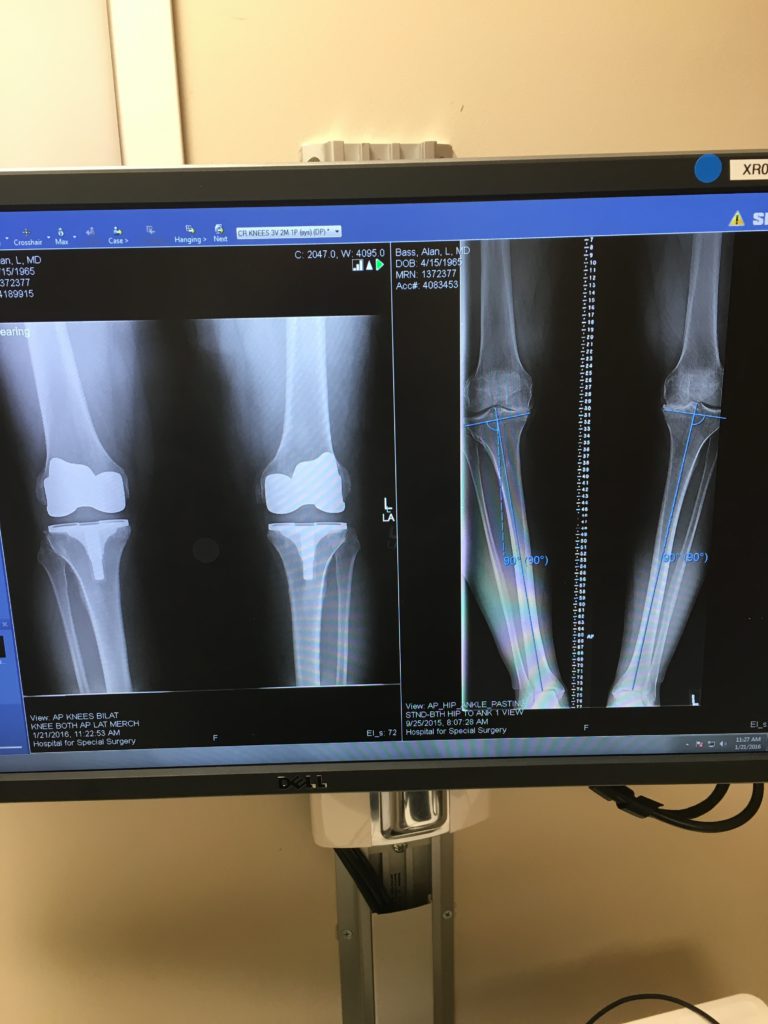

I've been a patient of an HSS rheumatologist for over 20 years, being treated for psoriatic arthritis. As a result of playing college football at the U of Maryland, I've had a series of knee injuries, which resulted in numerous surgeries over the years (7 total). My range of motion in both my legs became a major issue. I'm 64 years old and still live a very active life. I am an avid outdoorsman and participate in many activities such as hiking, biking, and my favorite, fly fishing. I also go to the gym regularly. The last few years I became unable to partake in these exercises because of the issues with my knees. My rheumatologist recommended Dr. Haas for bilateral knee replacement surgery. The surgery was performed on February 14, 2018. It's been one year since the operation and my recovery is remarkable. ALL the pain is gone and I'm able to participate in all of my favorite activities. Dr. Haas and his support team were remarkable. Also, the staff at HSS are true professionals. The entire experience was a blessing and I can't thank Dr. Haas and his crew enough!!!!!!